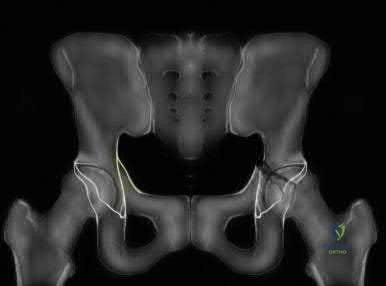

A 25-year-old male is brought to the emergency department after a high-speed motorcycle collision. He is hemodynamically unstable. A pelvic binder is appropriately placed. Radiographs reveal a rotationally unstable but vertically stable pelvic ring injury with symphyseal widening greater than 2.5 cm (APC-II pattern). Which of the following ligaments is predominantly disrupted at the sacroiliac joint in this specific injury pattern?

An Anteroposterior Compression Type II (APC-II) injury involves diastasis of the pubic symphysis > 2.5 cm, with disruption of the anterior sacroiliac, sacrotuberous, and sacrospinous ligaments. The posterior sacroiliac ligaments remain intact, maintaining vertical stability. Thus, at the sacroiliac joint, the anterior sacroiliac ligament is the one disrupted.